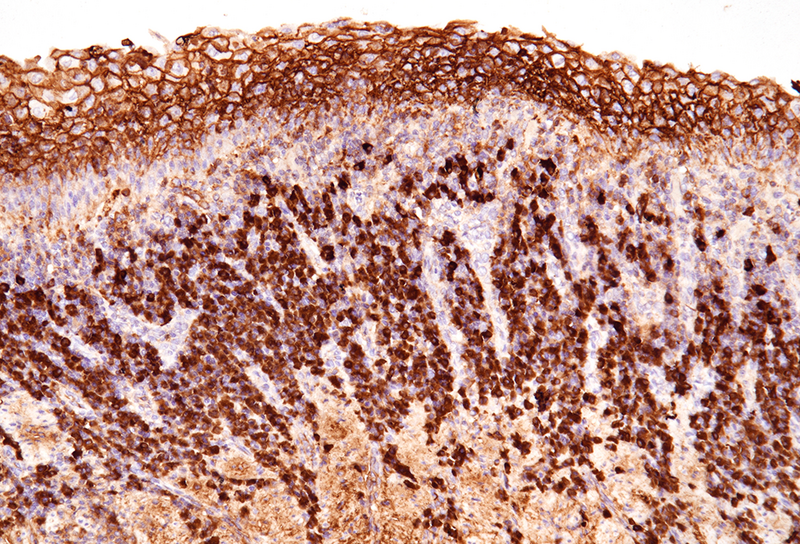

The microscopic examination of the resection specimen revealed diffuse lymphoplasmacytic infiltration throughout the oesophageal wall, with multiple lymphoid follicles and accentuation within the inner half (Panel A). On high magnification, diffuse infiltration of the overlying squamous epithelium by lymphocytes („lymphocytic oesophagitis pattern of injury”) and occasional plasma cells was observed (Panel B). The plasma cells were strongly positive for IgG and IgG4 (Panels C-D).